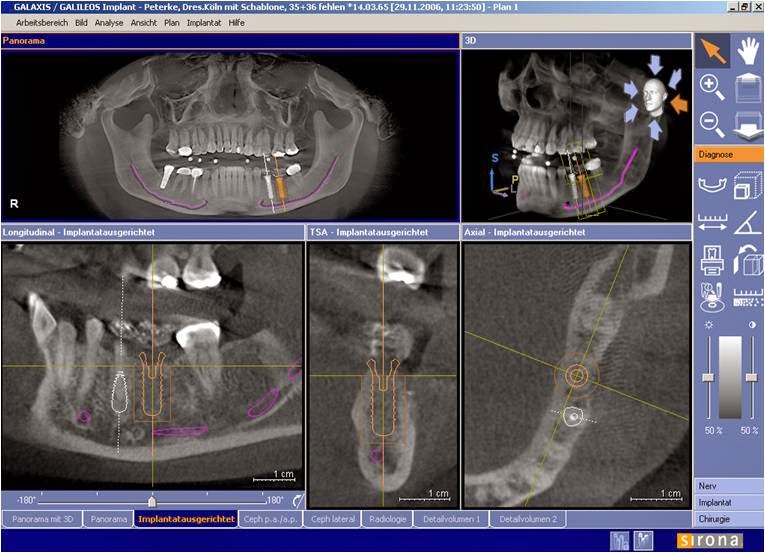

| Phim CTScan khảo sát xương định đặt implant. |